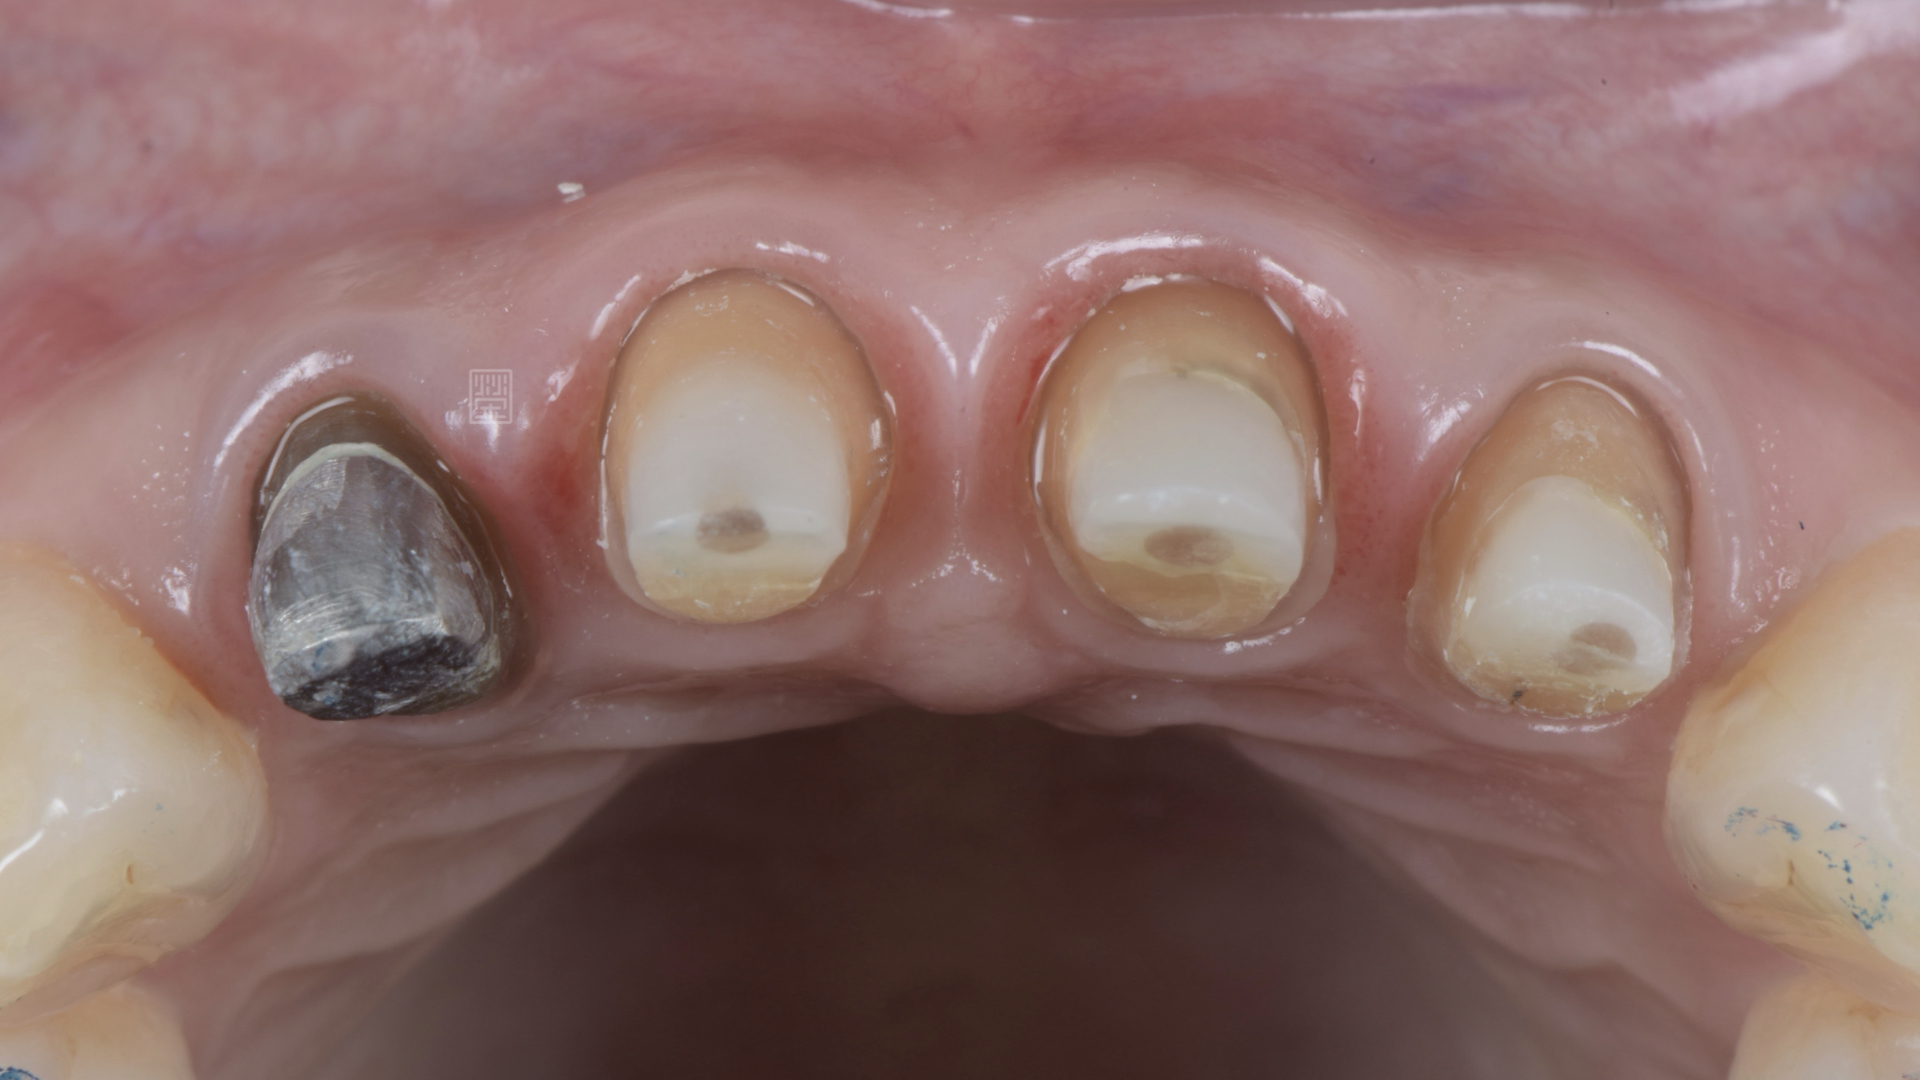

診斷後發現,主要是牙齦萎縮與牙根變色,加上門牙的長度不適合,所以讓整體笑容感覺沒精神。

全瓷冠邊緣變色

四顆門牙切端太平,曲度不足